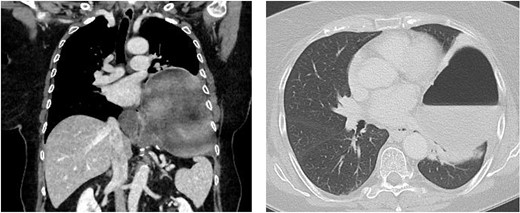

One day after admission, the patient developed massive dyspnea with a rapid deterioration of general condition. Chest X-ray showed a large left-sided tension seropneumothorax with a right-sided mediastinal shift (Fig. 2). Uncomplicated, ultrasound-guided chest drain insertion was performed immediately, and the clinical condition improved instantly. However, gastric secretion through the chest tube was observed and gastric perforation as a cause for the seropneumothorax was suspected. Therefore, emergency surgery was performed. A lift-sided antero-lateral thoracotomy was performed to rule out any lung parenchym lesions. Intraoperatively, a 2 × 2 cm gastric perforation was found (Fig. 3). After excision, the perforation was sutured, and the stomach was transposed into the intraabdominal cavity. Fibro-purulent empyema (stage II) was observed and local pleurectomy and decortication of the left lower lobe were performed. A transverse upper laparotomy was performed. After adhesiolysis due to massive adhesions following previous surgeries, hernia sac was excised, mobilization of the esophagus was carried out and crura were closed. Due to the present infection, no alloplastic material was used. A partial Watson anterior wrap was performed. There were no intraoperative complications. The patient was extubated in the operation room and transferred to the intermediate care unit for further observation. The postoperative course was uneventful, and patient was discharged in good condition on POD 7. Histological examination revealed a Helicobacter-positive gastric ulcer as a cause for gastric perforation. Two months after discharge, gastroscopy was performed and showed a normal finding with no signs of recurrence of the hiatal hernia.

Chest X-ray showing a large left-sided tension seropneumothorax with a right-sided mediastinal shift. Chest CT-scan after insertion of a chest tube.